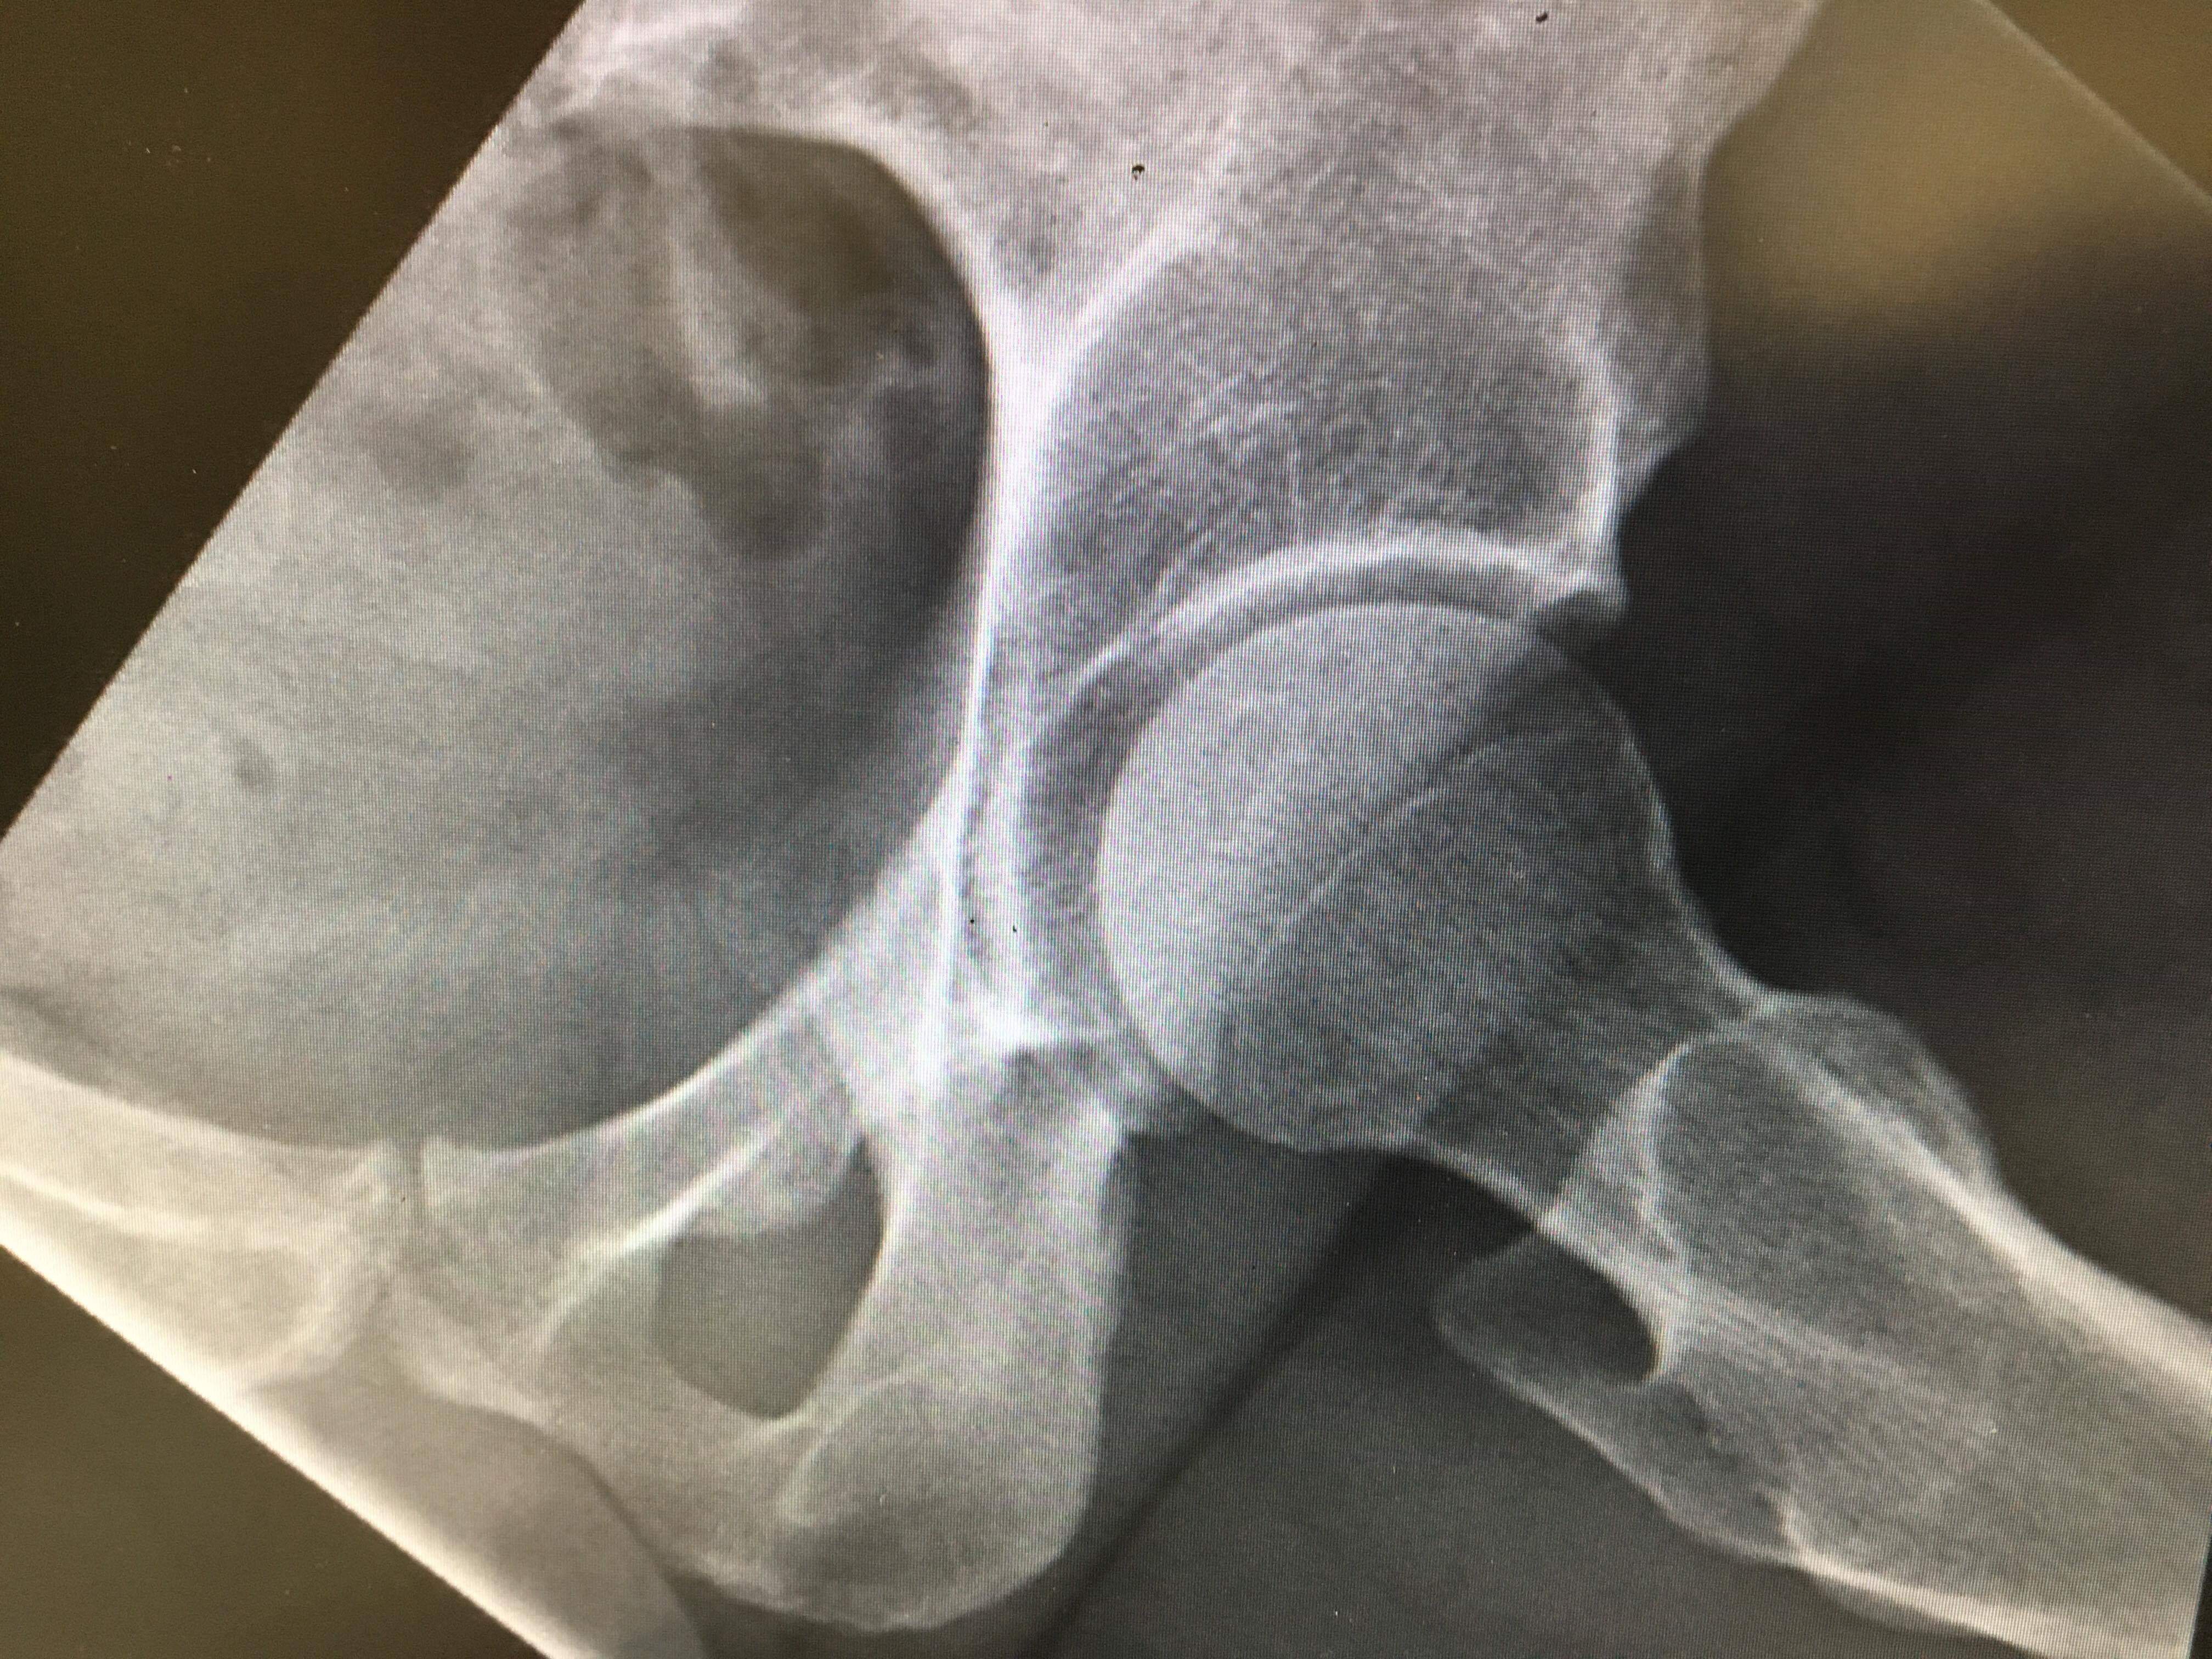

Charlotte’s Health Concerns: Charlotte has returned to her gardening job and is clearly enjoying being back among the plants. However, she has been experiencing hip pain for several years, and this week, a scan at a private hospital confirmed some worrying news. Her joints show significant signs of arthritis and wear, with larger-than-normal gaps in the ball-and-socket joints. The specialist has warned that she will likely need hip replacements by the time she is in her 40s and will require strong painkillers in the years to come.

She is understandably concerned that when the time comes, NHS waiting times may be lengthy or the surgery unavailable. If that proves to be the case, we will ensure she doesn’t suffer unnecessarily, even if it means going private. But for now, we take things as they come.